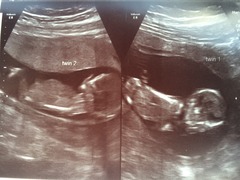

Attached are my latest scan pictures, they're both doing pretty well. I'm convinced I can feel the movement when I'm lay in bed very still and relaxed!

August 2016 (3) - scans fast approaching, teeny tiny bumps appearing, and sickness easing....we hope!